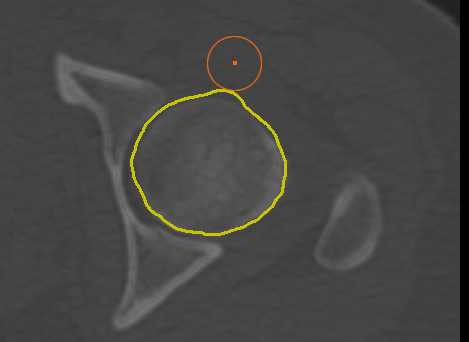

Adds a new path in Snap mode to the current group of paths. You use the Snap tool to create a path by simply dragging inside a feature on a 2D view. The contour line will automatically snap to the gradient that defines the edges of the targeted feature. Do the following to draw a path in Snap mode:

Generates a one-slice preview of the currently selected view that lets you evaluate the computed edge map and your Canny filtering and Gaussian filtering settings. Previews will appear as new items in the Data Properties and Settings panel. You can view a preview, shown below, by changing its visibility in the panel. |